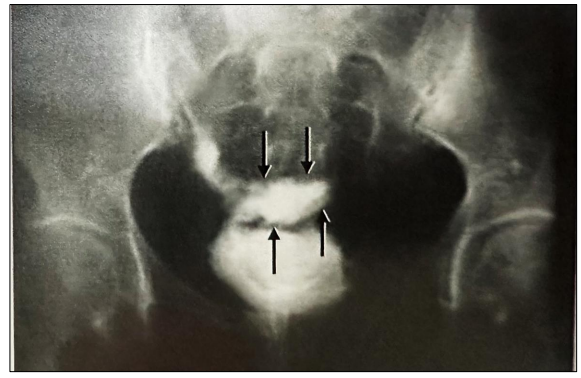

Paciente de 25 anos, G0, no 7º dia pós-operatório de videolaparoscopia para ressecção de focos de endometriose profunda, evoluindo com

dor lombar 7/10 e incontinência urinária. Realizada urografia excretora, que revelou a seguinte imagem:

Mediante o ora exposto, assinale a alternativa correta que apresenta o provável diagnóstico.